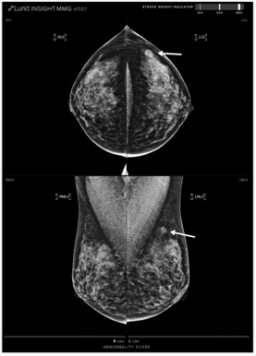

圖 一位44歲的患者被診斷為左乳有一個20毫米大小的三陰性亞型浸潤性導管癌,分期為T1cN0。左側乳腺癌在1點鐘方向表現為腫塊(箭頭),被AI-CAD遺漏(異常評分7分)